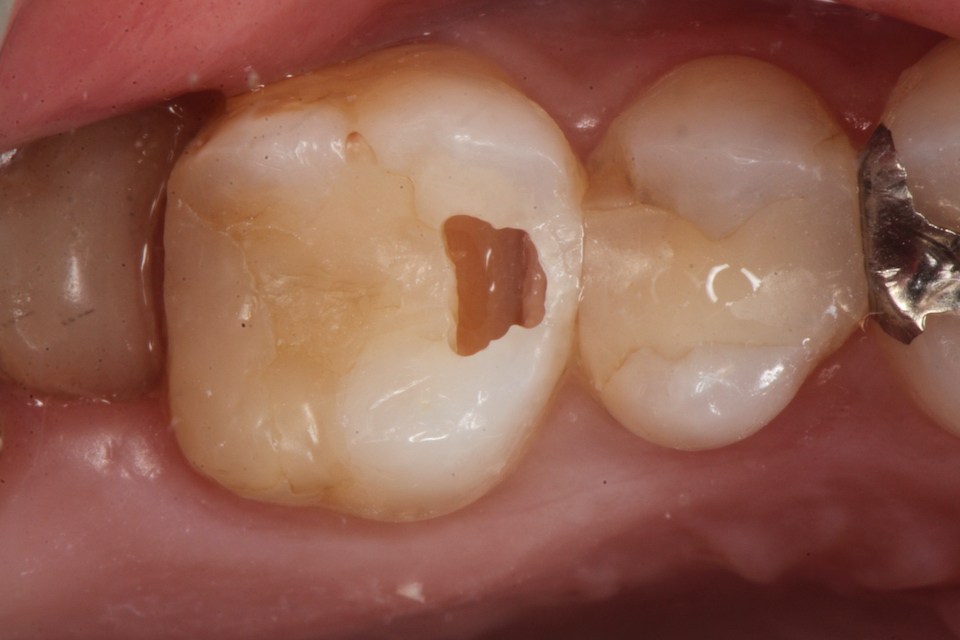

下顎7番の頬側歯茎部カリエスの原因 2025.06.04